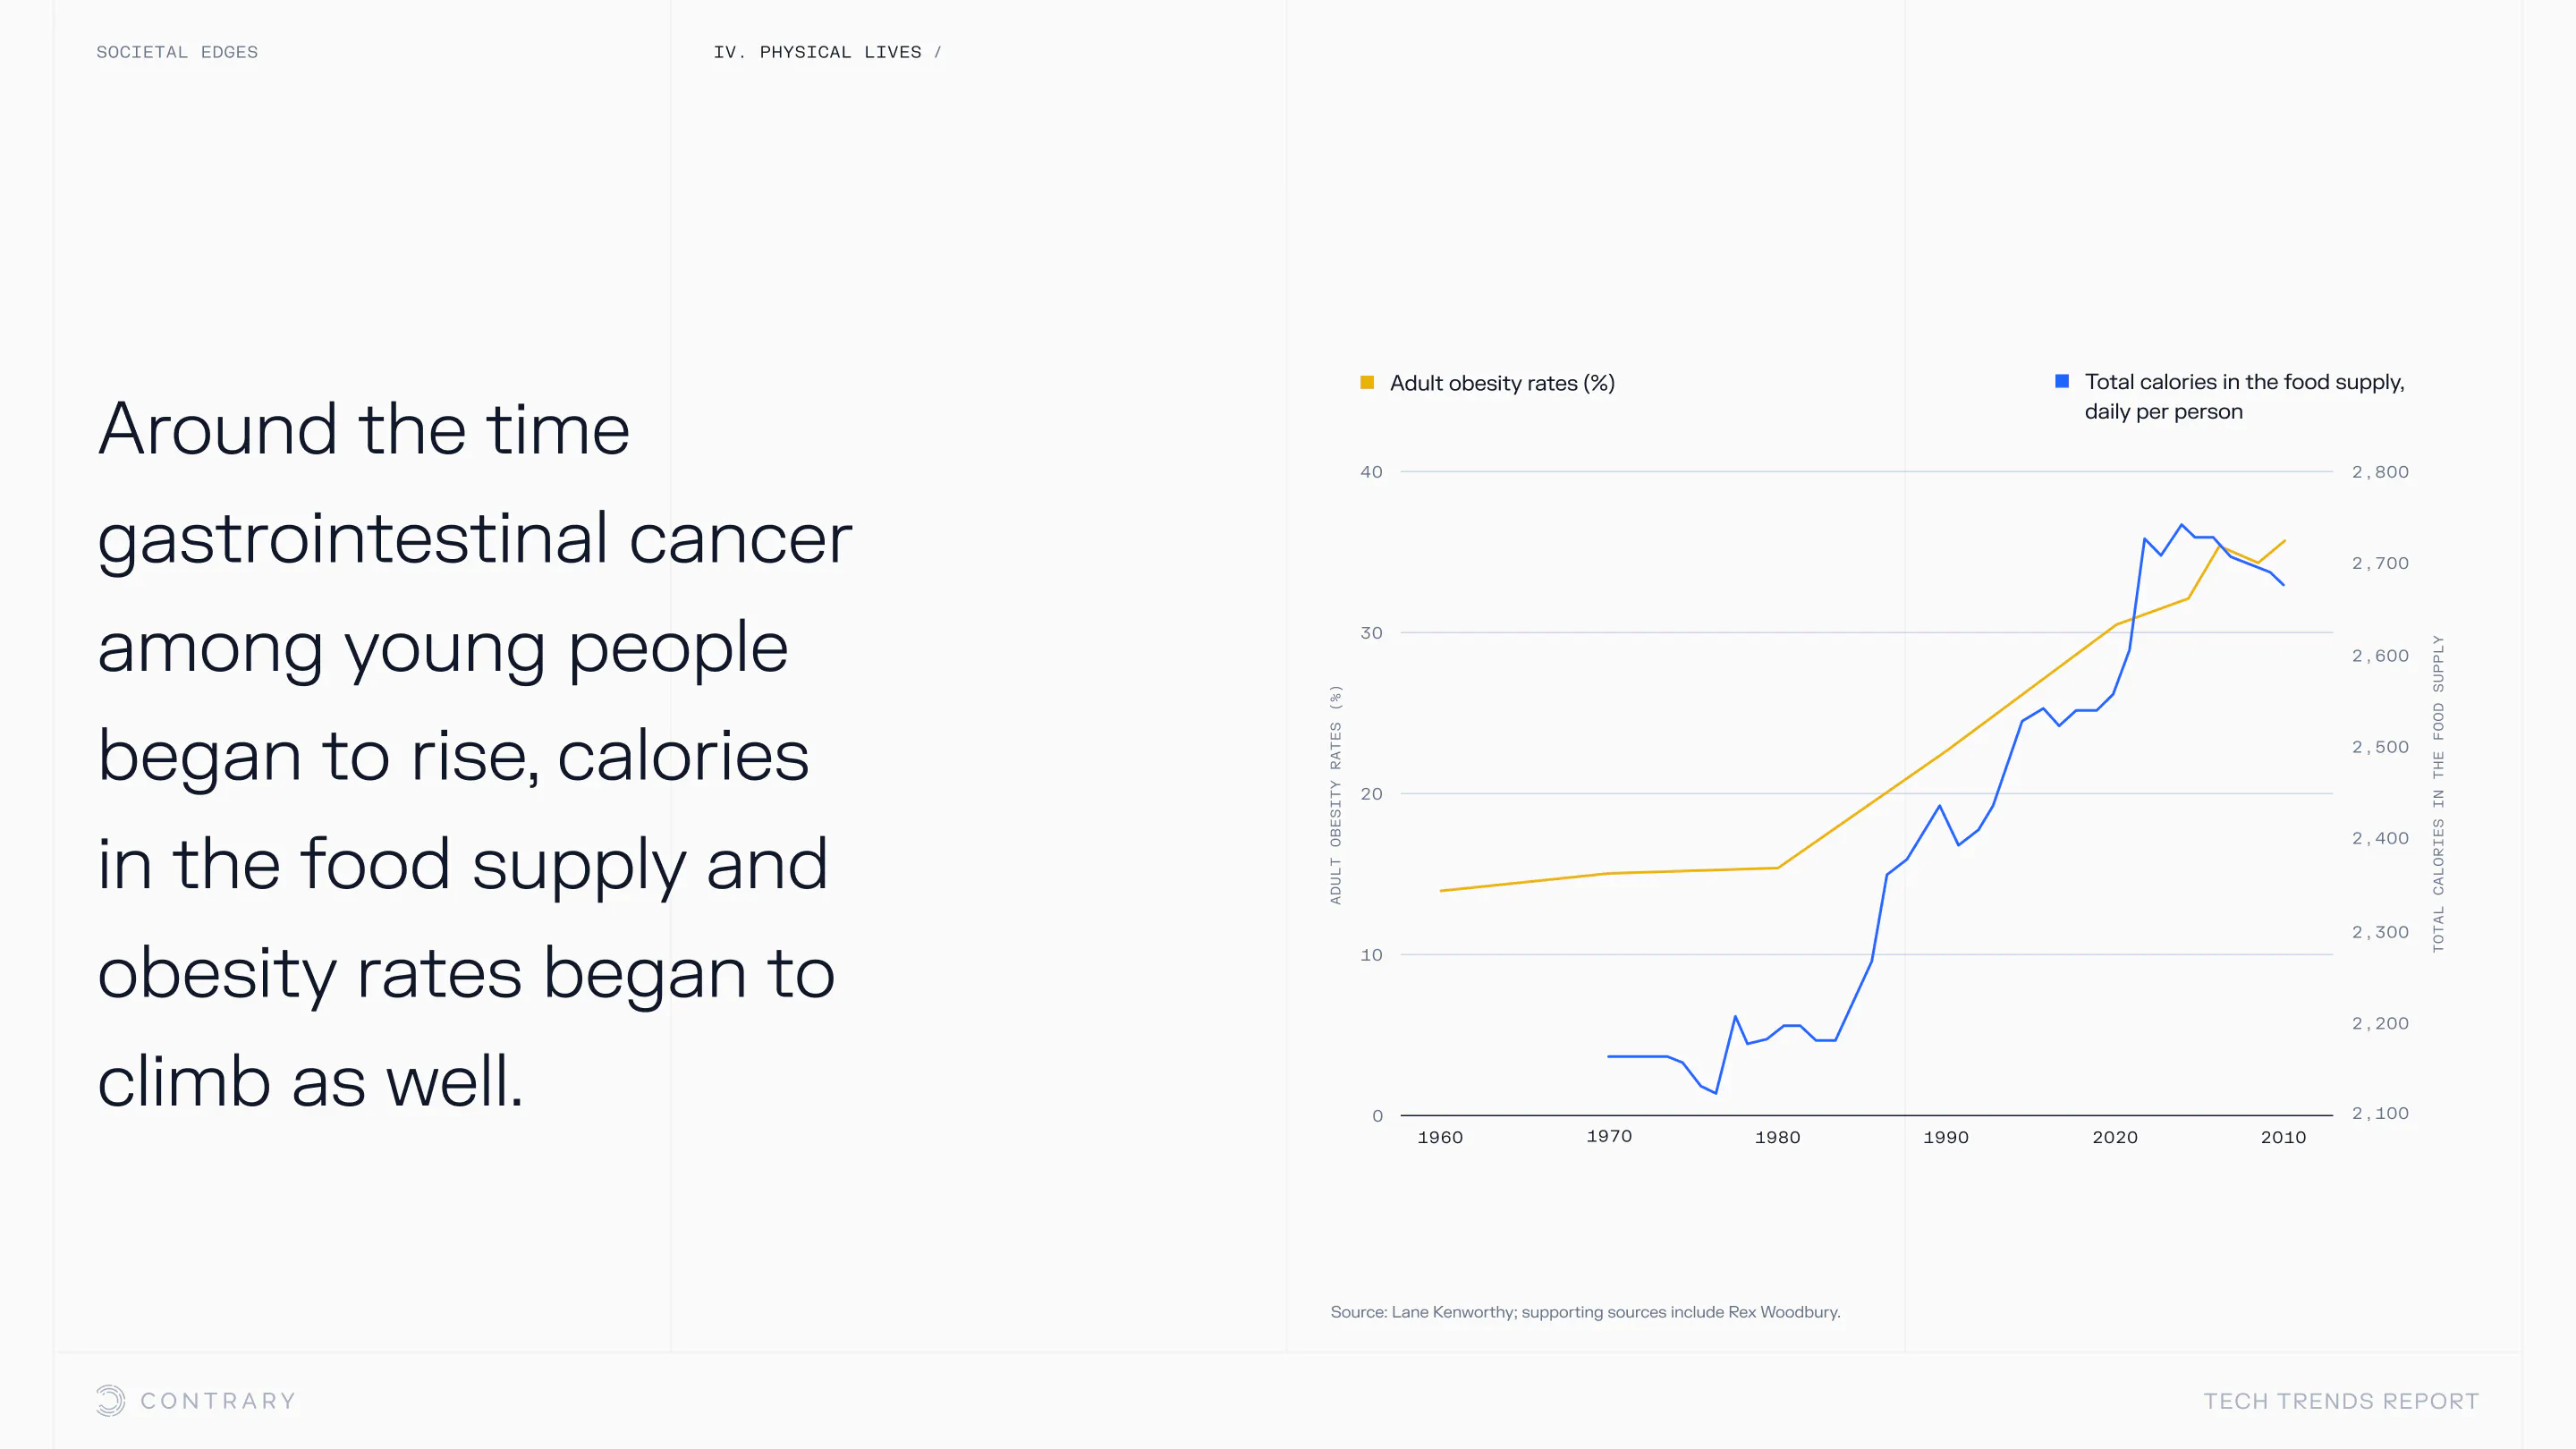

An aging population is bringing up a range of increased concerns, from mental health to disease control. Obesity and gastrointestinal cancers are plaguing younger generations. The cutting edge is tackling a system that has unhealthiness woven into it.